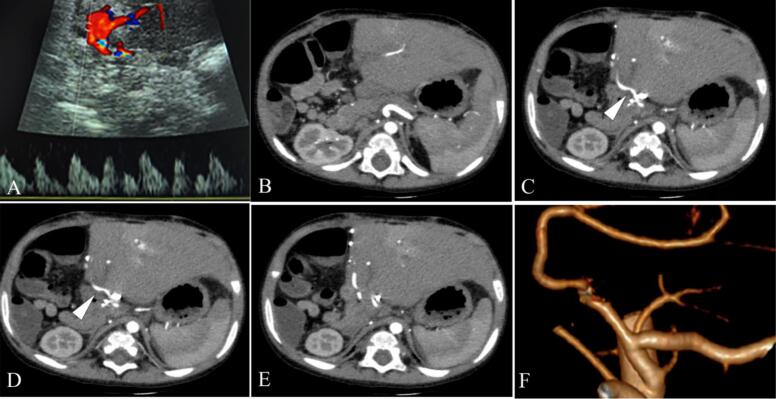

Presentation of case: A 13-month-old infant with biliary atresia post-Kasai procedure underwent living donor liver transplantation. On postoperative day 9, Doppler ultrasound detected signs of impending hepatic artery thrombosis, which was confirmed by computed tomography angiography. The patient was treated with intravenous alteplase at a dose of 0.3 mg/kg/h. After 3.5 hours of infusion, Doppler ultrasound showed improved hepatic artery flow. The infusion was stopped early due to intra-abdominal bleeding, which was managed conservatively. The patient stabilized without surgical intervention and was discharged on postoperative day 32 with stable hepatic artery flow. At six-month follow-up, the hepatic artery remained patent, and the patient was clinically stable.